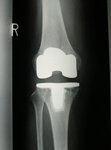

全人工膝関節置換術(TKA)

これは傷んだ軟骨、骨を人工膝関節の形に合わせて薄く削り、金属、セラミック、ポリエチレンでできた人工関節を自分の骨の上にしっかりと固定する手術です。約30年の歴史があり、日本でも年間約70000件の手術が行われています。手術治療の中で最も痛みをとる効果が高く、また変形の矯正が行え、成績の安定した手術です。

両側の変形性膝関節症の方で、左右同時に人工膝関節置換術をお受けになりました。手術前は両膝の痛みとO脚変形が強く、関節の伸びも曲がりもかなり制限されていましたが、手術後2週間で痛みは軽くなり、杖歩行も可能となりました。脚はまっすぐになって曲げ伸ばしも改善しました。